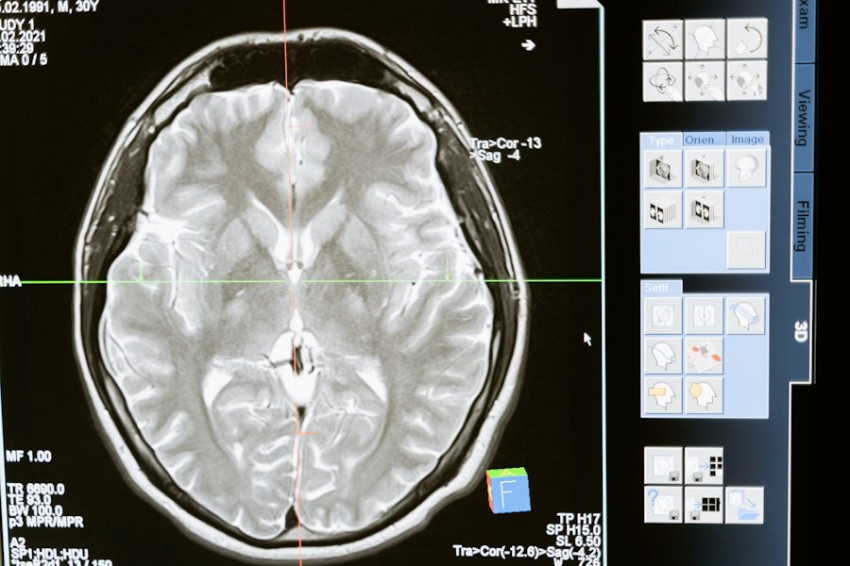

• Толстая кора головного мозга

• Крупные и активные нейроны, особенно в областях, отвечающих за память и внимание

• Большой объем гиппокампа

• Отсутствие дегенеративных изменений, характерных для болезни Альцгеймера